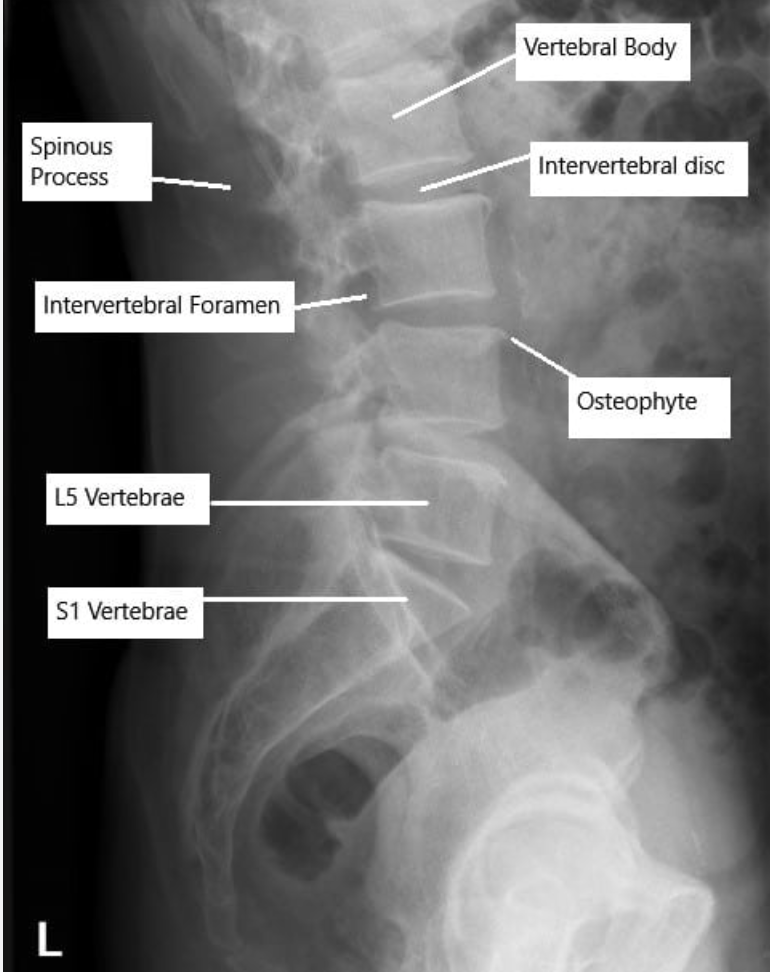

1. Lumbosacral spine X-ray (degenerative changes) show overgrowth of the facet joints, narrowing of the disc spaces, and osteophyte formation

2. CT spine/ MRI spine for closer inspection +/- surgical planning)